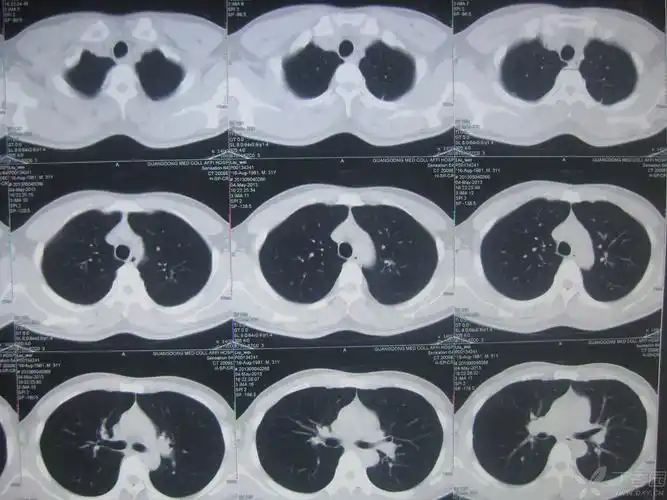

【求助】令人蛋疼的肺结核,请各位老师支招! [病例帖]